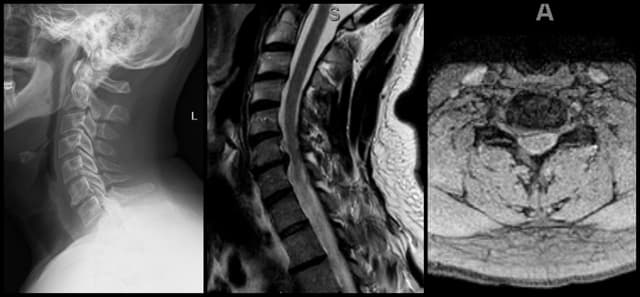

Imaging

Pre-op

Post-op